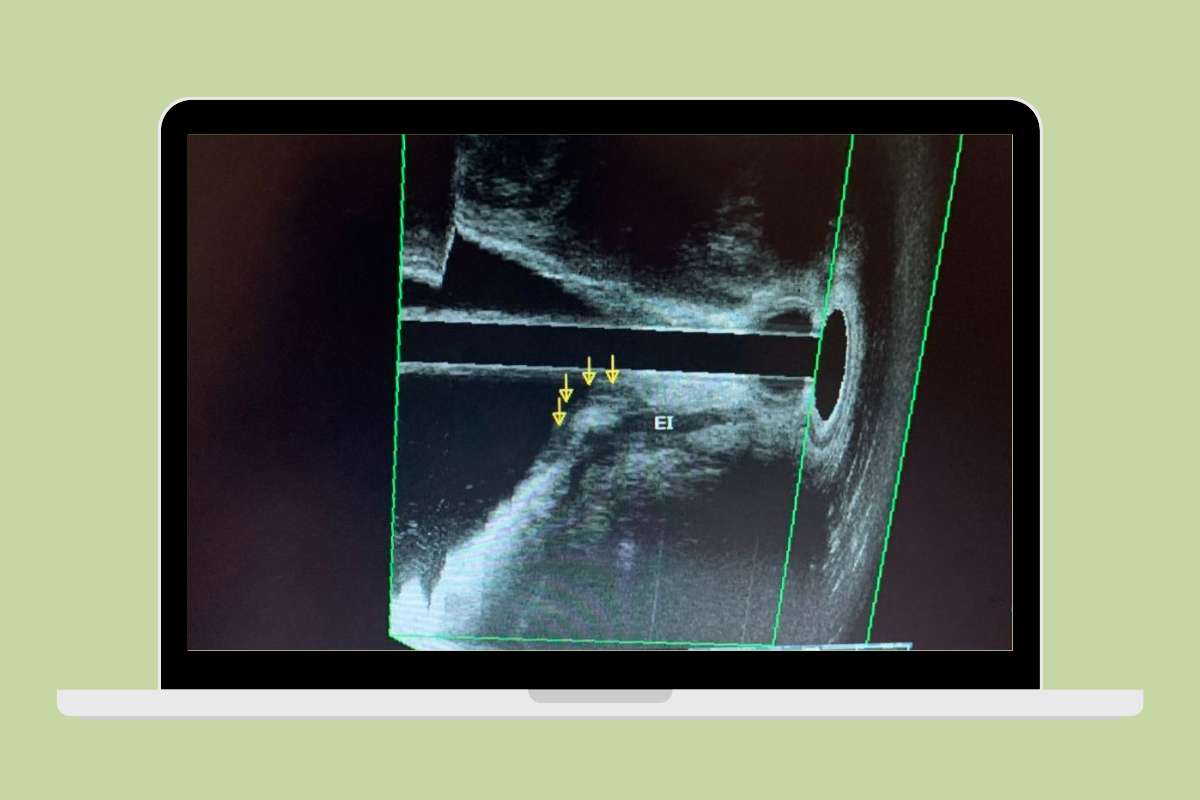

O procedimento respeita a fisiologia do ato evacuatório e permite visualizar cada fase do esforço, da contração ao relaxamento muscular.Atualmente, como a maioria dos serviços não dispõe mais do método, temos substituido a técnica através da ultrassonografia, tanto pela técnica de ecodefecografia quanto da ultrassonografia transperineal.